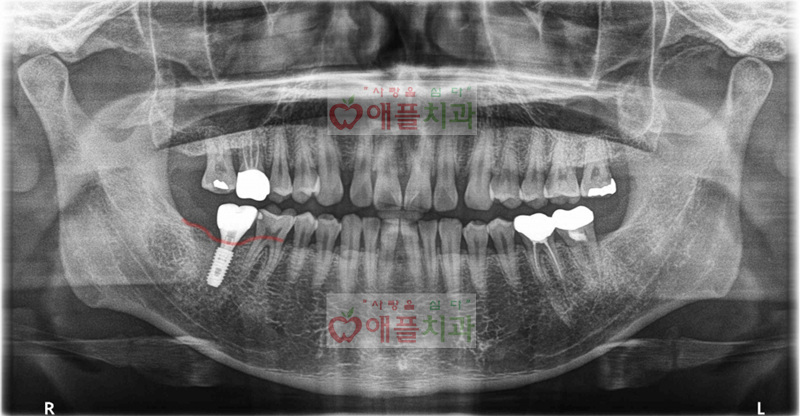

<골이식과 임플란트 완료후 엑스레이>

발치가 불가피하다고 설명드리면서 발치후 3개월 뒤에 임플란트 수술을 진행하였습니다. 잇몸뼈가 많이 흡수되어있어 골이식과 동시에 임플란트 수술을 진행하였습니다.

이 환자의 경우는 염증상태가 있기때문에 발치후 3개월을 기다렸습니다. 그리고 골이식을 하면서 동시에 임플란트 수술을 진행하였습니다.

결과는 환자도 의료진도 모두 만족한 결과였습니다.